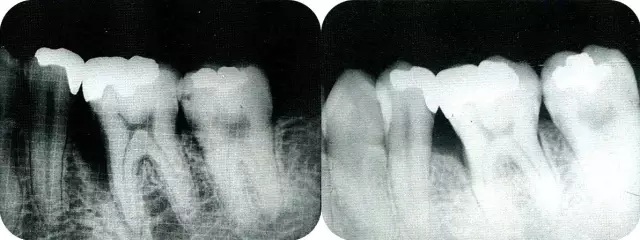

病例4  針對(duì)連續(xù)性骨缺損,利用2張非吸收性膜進(jìn)行再生治療的病例。

▲圖8-1  52歲,上班族,女性。來院主訴是左上橋體下部有空隙。

640.webp (8).jpg

▲圖8-2  初診時(shí)的x片。尖牙遠(yuǎn)中確認(rèn)有垂直性骨缺損。